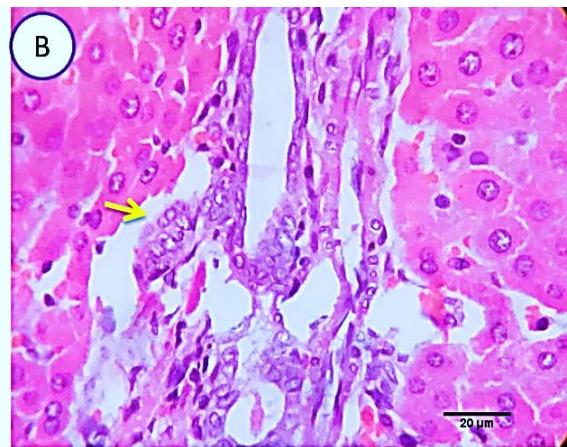

Fig. 3: Photo-micrograph from liver, group (2), showing, portal biliary proliferation (yellow arrow), congestions of portal blood vessels (blue arrow) and round cell infiltration beside degenerative changes in a few hepatocytes. Scale bars 120, 20 um.

Liver: Examined sections from liver of this group denoted moderate portal biliary proliferation, congestion of portal blood vessels, round cell infiltration, multifocal interstitial lymphocytic and macrophages aggregations replacing previous necrotic patches beside degenerative changes in a few hepatocytes. (Fig.4).